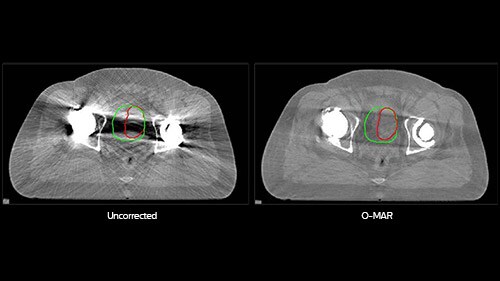

Bladder contour: O-MAR contour in red. Uncorrected contour in green. Volume difference: 32%. On the uncorrected images, the bladder was mostly obscured by the dark shadow caused by metal, so the physician overestimated the size of the bladder. On the O-MAR images, the size of the bladder was visible; there was no inter-observer variability.

O-MAR helps you see in the dark areas